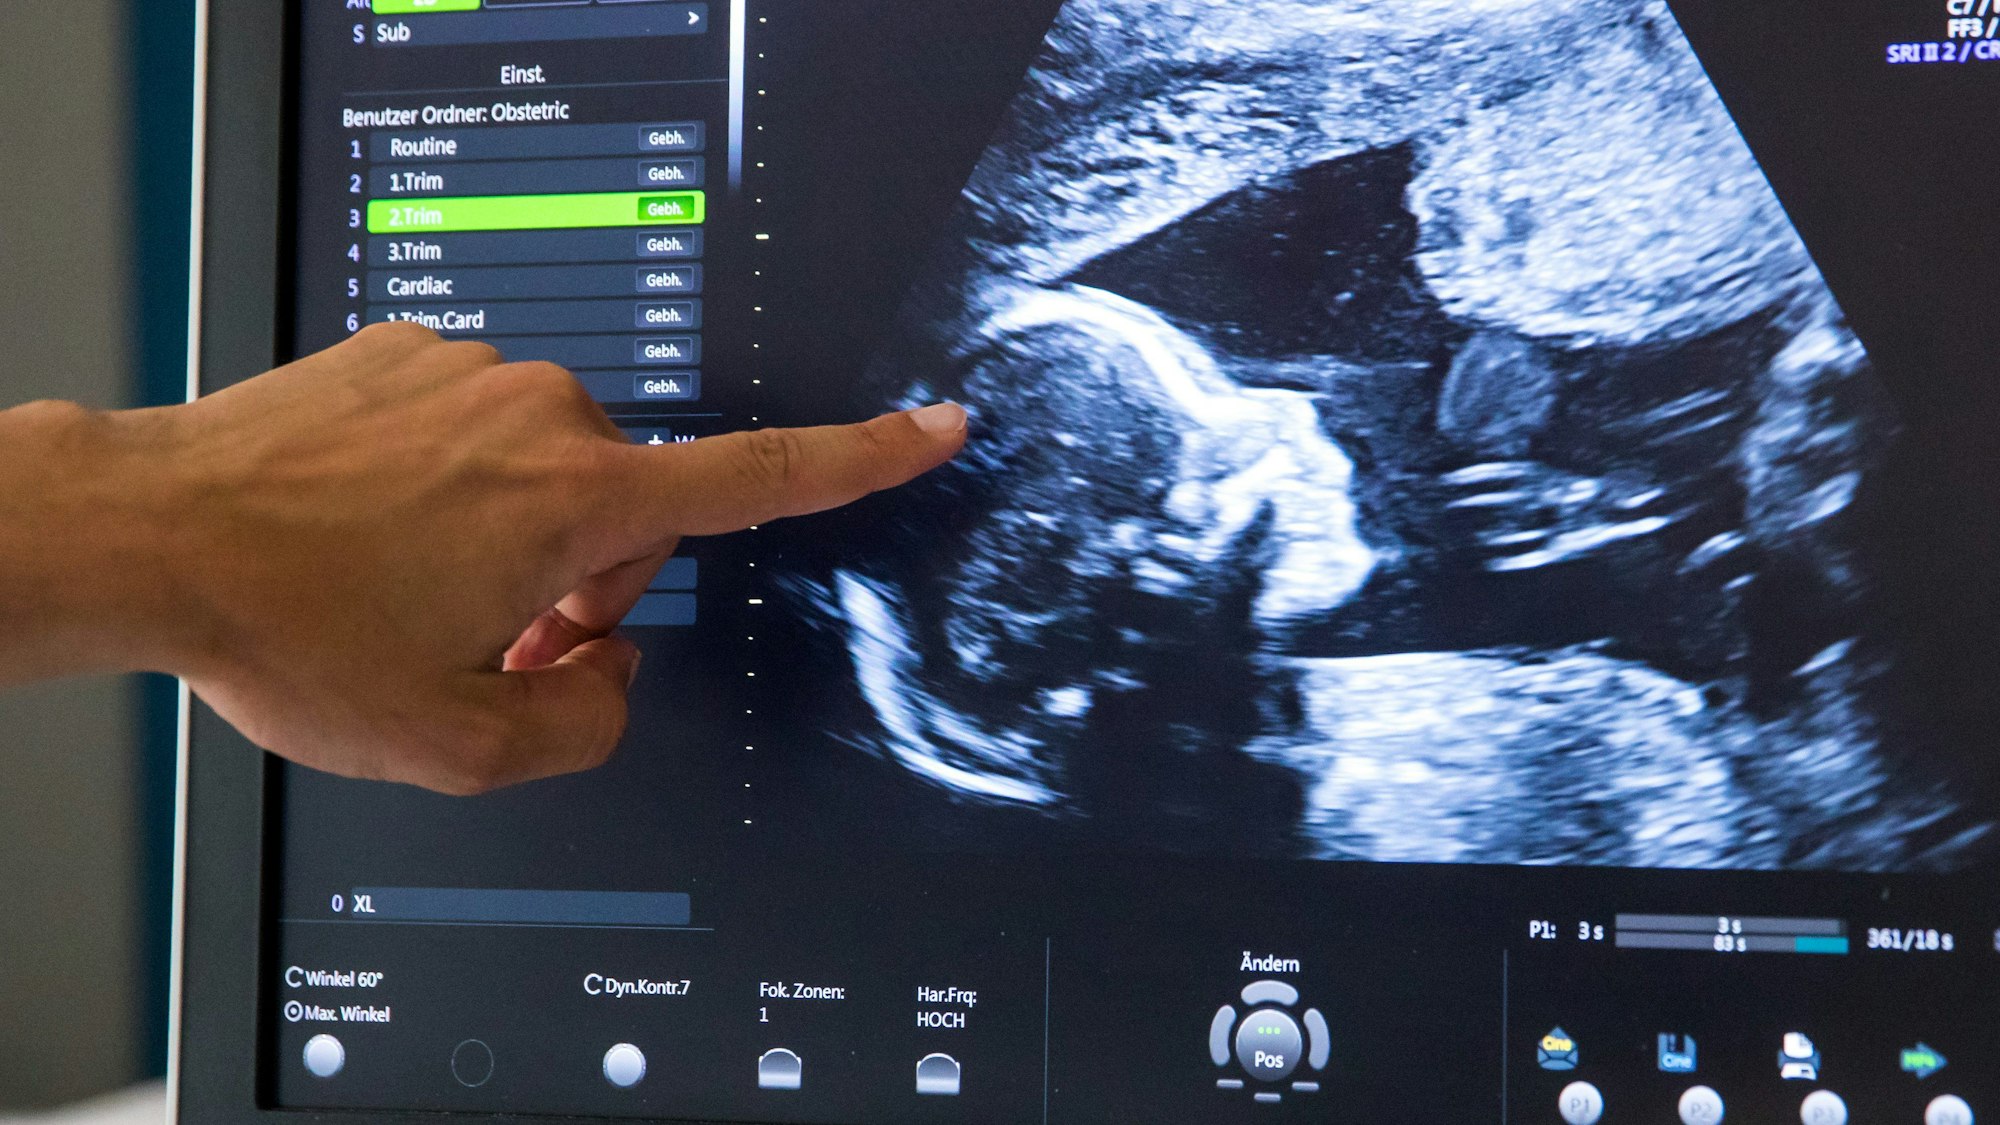

Kinder mit Krebserkrankungen haben eine Heilungschance von rund 80 Prozent, bei einem aggressiven Neuroblastom liegt die Überlebenschance jedoch nur bei rund 50 Prozent. Matthias Fischer forscht daran, dies zu verbessern. (Symbolbild)